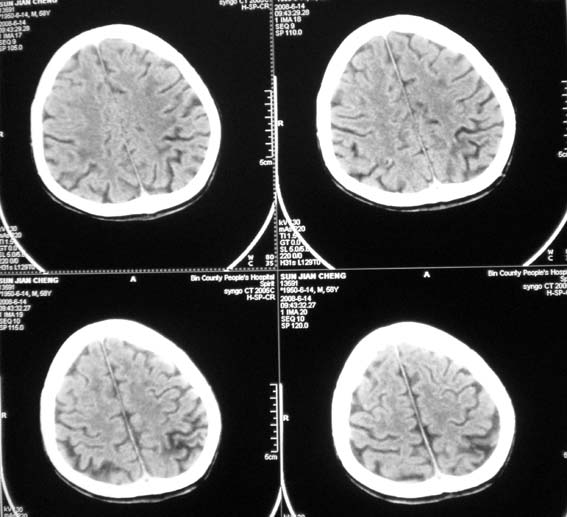

以下是引用王仕学在2008-6-14 22:17:00的发言:[br]左侧外侧裂池密度增高,考虑出血。

以下是引用随光逐影在2008-6-15 17:27:00的发言:[br]1)脑积水引流术后导管留置。2)蛛网膜下腔出血。3)左侧基底节区及左侧额叶多发脑腔隙灶。4)脑萎缩。

以下是引用dyqct在2008-6-15 10:32:00的发言:[br]支持:1、左侧外侧裂池密度增高,考虑出血。[br] 2、左侧基底节区脑软化灶。